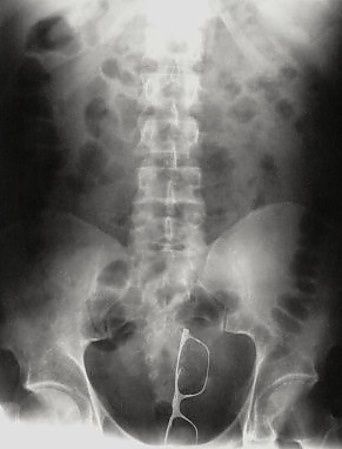

Malum Bölgelerine Kazayla Giren Nesneler Sonucu Acile Kaldırılmış İnsanların 15 Röntgen Görüntüsü  Bu nesnelerin orada olmasının mantıklı hiçbir alakası yok. Büyük ihtimalle bir kaza sonucu bu durum oluşmuştur. Aksini düşünmek bile istemiyorum. Foto Galerimizin devamını görmek için Lütfen sonraki sayfaya geçiniz..